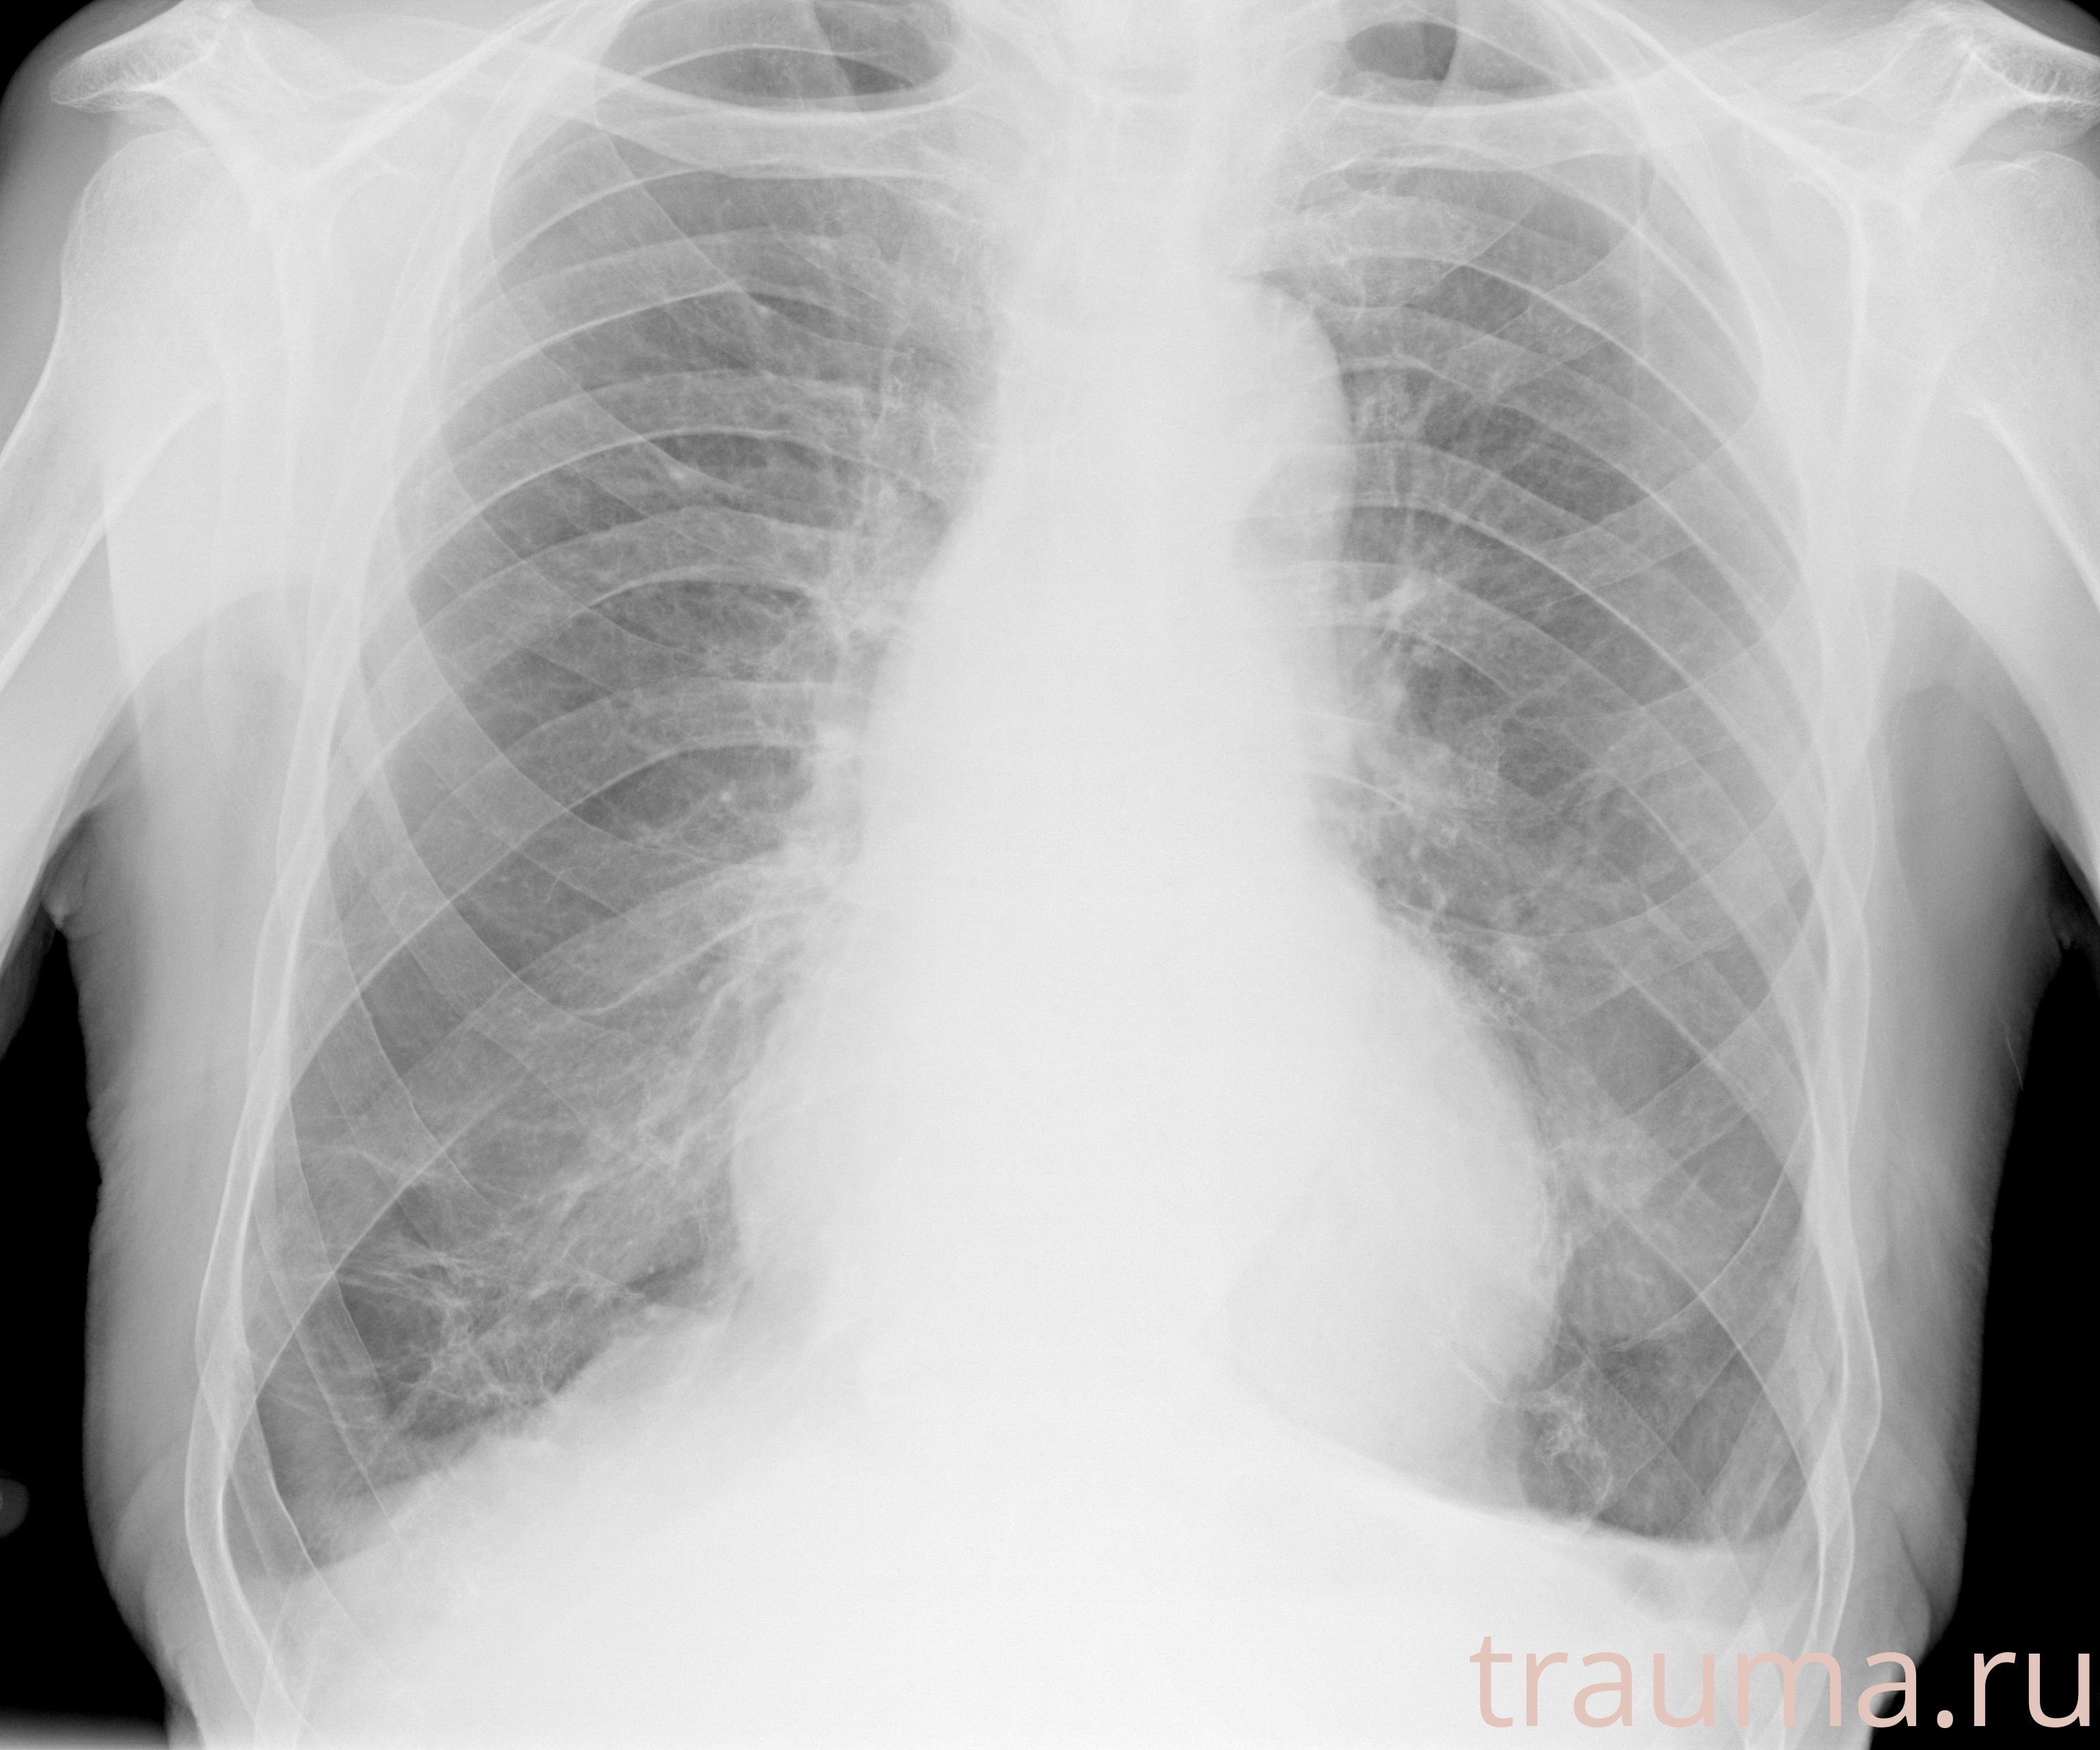

Рентгенограммы

Рентген на дому: по вашему адресу приезжает врач-рентгенолог, травматолог-ортопед с мобильным рентгеновским аппаратом, проводит диагностику травмы или заболевания, делает необходимые рентгенограммы, дает рекомендации по дальнейшему лечению. Получить качественные снимки в домашних условиях возможно благодаря уникальной методике, разработанной МосРентген Центром для института  Склифосовского